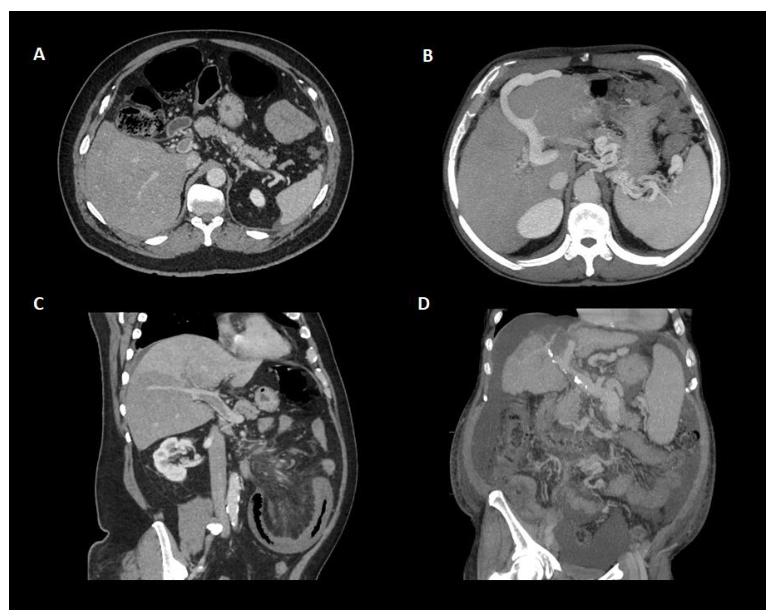

关于门静脉血栓的“年龄”,近期门静脉血栓的特征包括低回声和低密度血栓,门静脉平扫时门静脉密度增加,门静脉密度增加,增强CT扫描中心透明。相关的肝脏血流灌注改变也可以表现为动脉期肝实质增强,门脉期增强减弱。相反,血栓壁内的钙化和海绵状肿瘤的存在提示慢性(图3)。必须指出的是,前者只能用US或CT发现,而不能用MR检查,而且在PVT发病后1-3周内可发生海绵状改变(图4)。

图3.CT增强扫描门静脉血栓形成的不同表现。(A)轴向面显示门脉主干部分闭塞性门静脉血栓形成,无侧支或其他门脉高压间接征象。(B)门静脉血栓形成时出现侧支循环伴脐静脉再开放和脾脏肿大。(C)斜平面示门脉主干部分闭塞性门静脉血栓形成,右叶下段肝灌注缺损。(D)肝硬化患者的慢性门静脉血栓形成。注意门静脉钙化是慢性的间接征象。萎缩性肝伴脾肿大、侧支和腹水常出现在肝硬化的情况下。